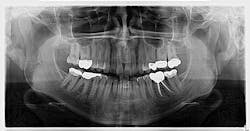

An assessment of the pan revealed two radiopaque lesions apical to the root tips of nos. 8 and 9, each measuring approximately 8 mm x 4 mm (figure 1). There was no tenderness on palpation in the generalized area. Access to a previous pan taken six years prior revealed no significant changes to the radiopacities (figure 2).

Given the location, absence of change, and shape of the lesions, the diagnosis for these lesions is mesiodens, a “supernumerary tooth located between the maxillary central incisors.”1 The lesions may occur “as single, multiple, unilateral, or bilateral (lesions); the presence of multiple supernumerary teeth is called ‘mesiodentes.’”2 By way of appearance, they typically manifest as a conical or peg-shaped form.2